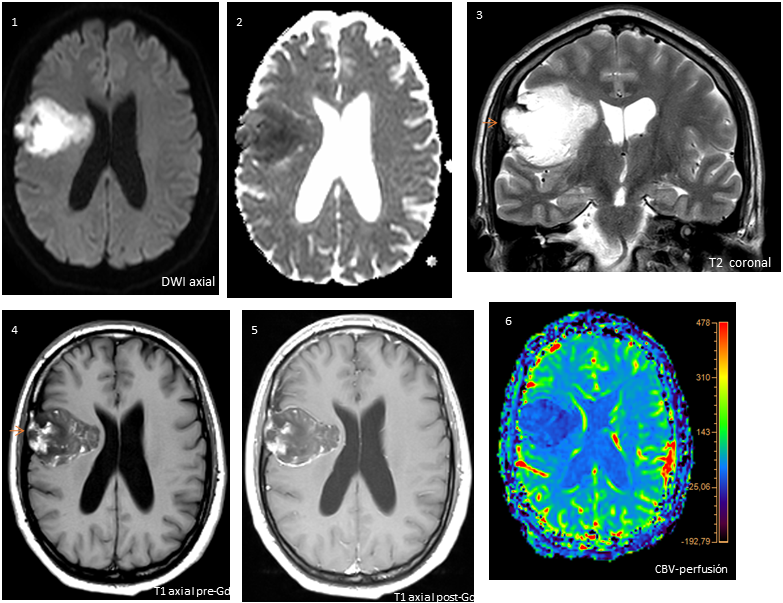

Lesión expansiva extraaxial a nivel de opérculo frontal derecho con restricción de la difusión (fig.1-2), señal heterogénea en T1 (fig.4), hiperseñal T2 (fig.3), mínimo relace periférico , sin aumento de CBV en estudio de perfusión ni edema vasogénico asociado. La lesión condiciona moderado efecto masa con leve desviación de línea media (3 mm), impronta parénquimatosa alcanzando región paraventricular y remodelación ósea de tabla interna–diploe frontal derecho (felchas rojas).

Quiste epidermoide (localización inusual)

En RM éstas lesiones pueden tener señal variable dependiendo del contenido, siendo lo más característico hiposeñal T1 e hiperseñal T2 (similar a LCR), restricción de la difusión (secundario al contenido de queratina, debris y colesterol) y ausencia de realce o mínimo realce periférico. Es menos frecuente que presenten hiperseñal T1 /hiposeñal T2 (proteinas altas, hemorragia) y calcificaciones.